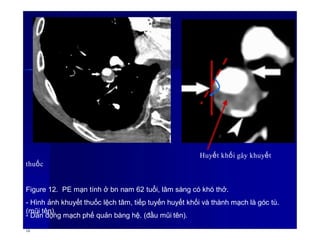

Huyết khối gây khuyết

thuốc

Figure 12. PE mạn tính ở bn nam 62 tuổi, lâm sàng có khó thở.

- Hình ảnh khuyết thuốc lệch tâm, tiếp tuyến huyết khối và thành mạch là góc tù.

(mũi tên).

- Dãn động mạch phế quản bàng hệ. (đầu mũi tên).

16